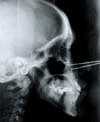

Cefalométricamente en la proyección lateral se marco el punto de mayor proyección del malar y el punto infraorbitario con señaladores metálicos.

Se tomaron las medidas angulares SN-Or (Or=orbitale), SN-M (M=mayor proyección del hueso malar)y SN-I (I=infraorbitale).

También tomamos las medidas lineales Or 1 NA, M 1 NA, I 1 NA, Po-Or. , así se obtuvo la forma y posición en sentido A.P. del malar (figuras No. 5 y 6).

Figura No. 5 Toma de cefalometría marcando malar con señaladores metálicos

Figura No.6 Cefalometría con marcadores metalicos